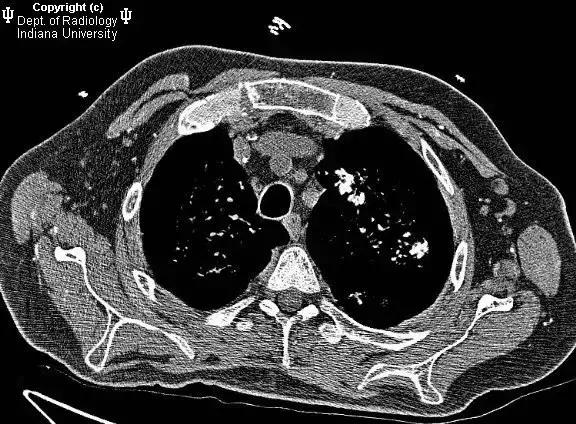

两肺索条、钙化,必要时定期复查

索条:指纤维性病变或纤维化,常见于慢性炎症或增殖性病变在修复愈合过程中,纤维成分逐渐代替细胞成分而形成瘢痕。说的再简单点就是“疤瘌”。

钙化:多属变质性病变,破坏的局部组织内钙盐沉积所致。说简单点就是各种原因导致的钙质在不该沉积的地方沉积了。

两者都属于陈旧性病变的范畴,要结合其它影像学征象和临床表现确定病因,建议1年复查一次。若医生考虑是结核病所致,一旦患者有临床症状应即刻复查;如果病变范围增大或钙化密度减低时,也要进一步检查。

Fig 2 肺内条索

Fig 3 肺内钙化